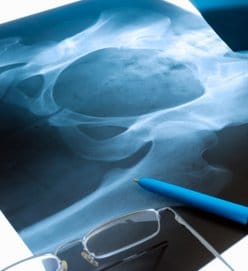

ה- American College of Rheumatology מעדכן את ההנחיות לטיפול ב- glucocorticoid-induced osteoporosis בקרב מבוגרים וילדים. להלן עיקרי ההמלצות:

• עבור כל החולים, יש להעריך את הסיכון לשברים בתוך שישה חודשים לכל המאוחר לאחר תחילת הטיפול בגלוקוקורטיקואידים. ההערכה צריכה לכלול פרטים על מינון הטיפול, היסטוריית השברים, צפיפות העצם, מחלות רקע, גובה ומשקל, ועבור מבוגרים מגיל 40 ומעלה, השימוש ב- FRAX tool.